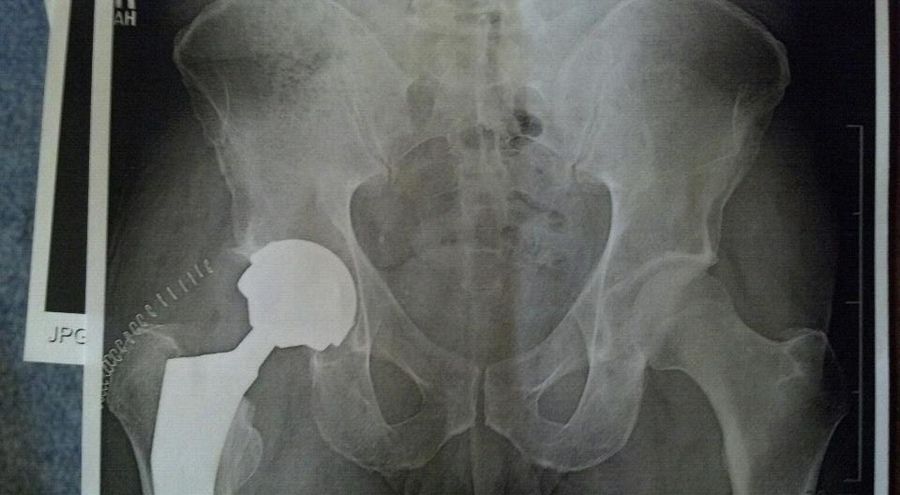

Good thoughts welcome....DH is going in for his hip replacement this afternoon. He's only 38, but has severe degeneration of the joint - the xrays are pretty ugly, and the doctor was surprised he can walk, let alone climb trees every day (he's a line clearance tree trimmer). Luckily, it's only his one hip, the other is in good shape. He'll be off work for up to 3 months (due to his work, he can't go back until he's 100% healed, no "easy" jobs for him to do, it's all go the day he goes back). He's hoping he can be ready to go in two months.

This will be his first surgery under anesthetic, and his first hospital stay. He's pretty positive about it. He'll be getting a metal on metal implant instead of the ceramic or plastic, doctor thinks the metal on metal will be best due to his young age and his line of work. Doc is confident he will be able to return to his job and do it for a long time (until he retires, which is good as he's going to be on a pension, and doesn't have a 401k).